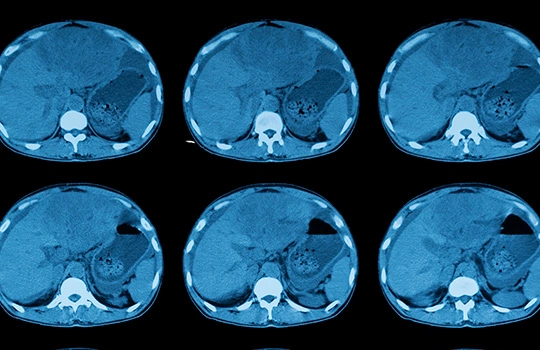

Above: A 68-year-old woman with a 10-year history of liver dysfunction. Previous tests showed significant metabolic decline and toxin buildup, indicating impaired liver function.

Above: The patient's tests after using the Yoofibre show significant improvement in liver function, with detoxification and metabolic health greatly enhanced, approaching the levels of a healthy liver.